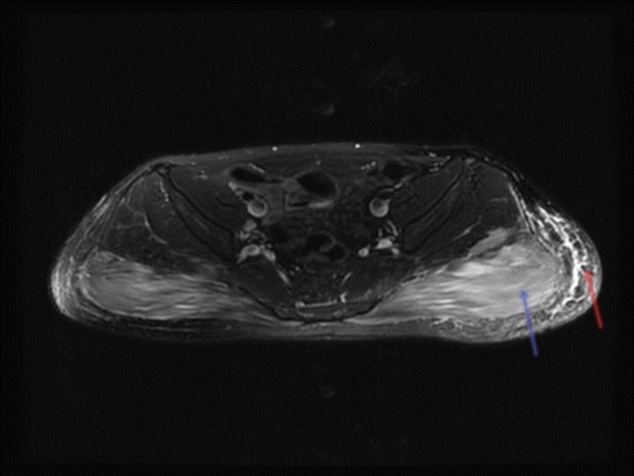

Unlabelled: Methimazole is an anti-thyroid drug commonly used to treat hyperthyroidism and is a relatively safe medication. Several side effects have been reported and usually develop within 3 months of therapy. Well-known adverse reactions include agranulocytosis, hepatitis, skin eruptions, and musculoskeletal complaints such as myalgia, arthralgia, and arthritis. So far, myositis secondary to carbimazole was described in the context of a lupus-like syndrome or other rare cases of anti-neutrophil cytoplasmic antibodies-associated vasculitis. Methimazole-induced myositis occurring independently of such reactions was rarely stated. We report a patient with hyperthyroidism who, early after therapy with methimazole, developed hepatitis, eosinophilia, and fever that resolved completely after stopping the medication as well as a delayed onset of biopsy-proven eosinophilic myositis and fasciitis of gluteal muscles that resolved eventually without any additional therapy. Therefore, we raise the awareness regarding a rare side effect of methimazole: myositis.

Learning points: Several differential diagnoses arise when managing a hyperthyroid patient with muscle complaints.Both hyperthyroidism and methimazole are associated with myositis.Methimazole-induced myositis is a rare clinical entity.Resolution of symptoms may occur after stopping methimazole.